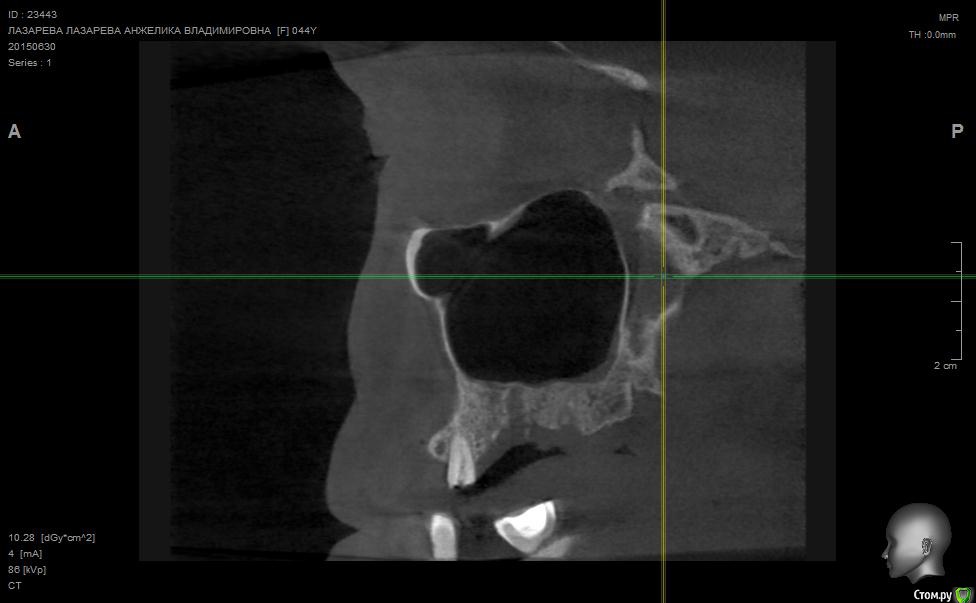

Angelika Опубликовано 2 июля, 2015 Поделиться Опубликовано 2 июля, 2015 Добрый день!Помогите,пожалуйста!!!!!!8 мая имплантолог(!) удалил 2 зуба-27(резерцин-формалиновый) и 28 (нелеченный).Удаление было очень долгим и травматичным,почуяв неладное,хотела убежать прямо из кресла.Последствия-одонтогенный гайморит,не считая незаживающих лунок .В начале июня отлежела в ЧЛХ(антибиотики,физио).26 июня сделала КТ.Нос пришел в норму более-менее,а вот челюсть....((((( Из заключения: 26,27,зубы отсутствуют. В альвеолярном отростке верхней челюсти в области отсутствующего 26 и 27 зуба визуализируется дефект костной ткани размерами до 9,6*14,0*7,2 мм с неровными и нечеткими контурами, с множественными мелкими и крупными секвестрами, с разрушеннымиоральной кортикальной пластинкой альвеолярного отростка верхней челюсти на протяжении до 12,9мм, и вестибулярной замыкательной пластинкой на протяжении до 19,1 мм. Рентгенологическихпризнаков свидетельствующих о наличии свищевого хода, ороантрального соустья - не выявлено,целостность нижней стенки левой верхнечелюстной пазухи полностью восстановлена на всем протяжении. Положительная динамика от 26.05.15г. В альвеолярном отростке, в области корней отсутствующего 28 зуба, определяются нечеткиеконтуры лунки удаленного зуба и единичный фрагмент корня размерами до 1,9*1,7*2,7 мм. В областиотсутствующего 28 зуба и бугра верхней челюсти слева визуализируются единичные мелкие участки остеопороза костной ткани альвеолярного отростка верхней челюсти, в следствие исхода воспалительного процесса. Посоветуйте,пожалуйста,нужно ли удалять обломок корня 28 зуба,если он такой маленький,а лунка уже затянулась.Что мне делать,как это залечить,болит вся челюсть с левой стороны.(((((( О имплантах и забыла уже,восстановиться бы после такой травмы.....Помогите!!! Что делать,как залечить все это?Снимки прилагаю. Ссылка на комментарий

Alejandro Опубликовано 2 июля, 2015 Поделиться Опубликовано 2 июля, 2015 На бумаге страшнее, чем на снимке. Лучший врач для Вас теперь - время. Со временем, кстати, станет понятно: что делать с остатком корня, экстренности пока никакой нет. Успокойтесь, сложные удаления довольно часто встречаются. Очень хорошо, что нет ороантрального сообщения. 2 Ссылка на комментарий

Bier Опубликовано 5 июля, 2015 Поделиться Опубликовано 5 июля, 2015 нет. У Вас на рентгене картина свежего удаления. Т.е. в рамках нормы 2 Ссылка на комментарий

Bier Опубликовано 7 июля, 2015 Поделиться Опубликовано 7 июля, 2015 думаю, что проблем там нет. На снимке все не так плохо, как в описании. Все хорошо будет. Ссылка на комментарий